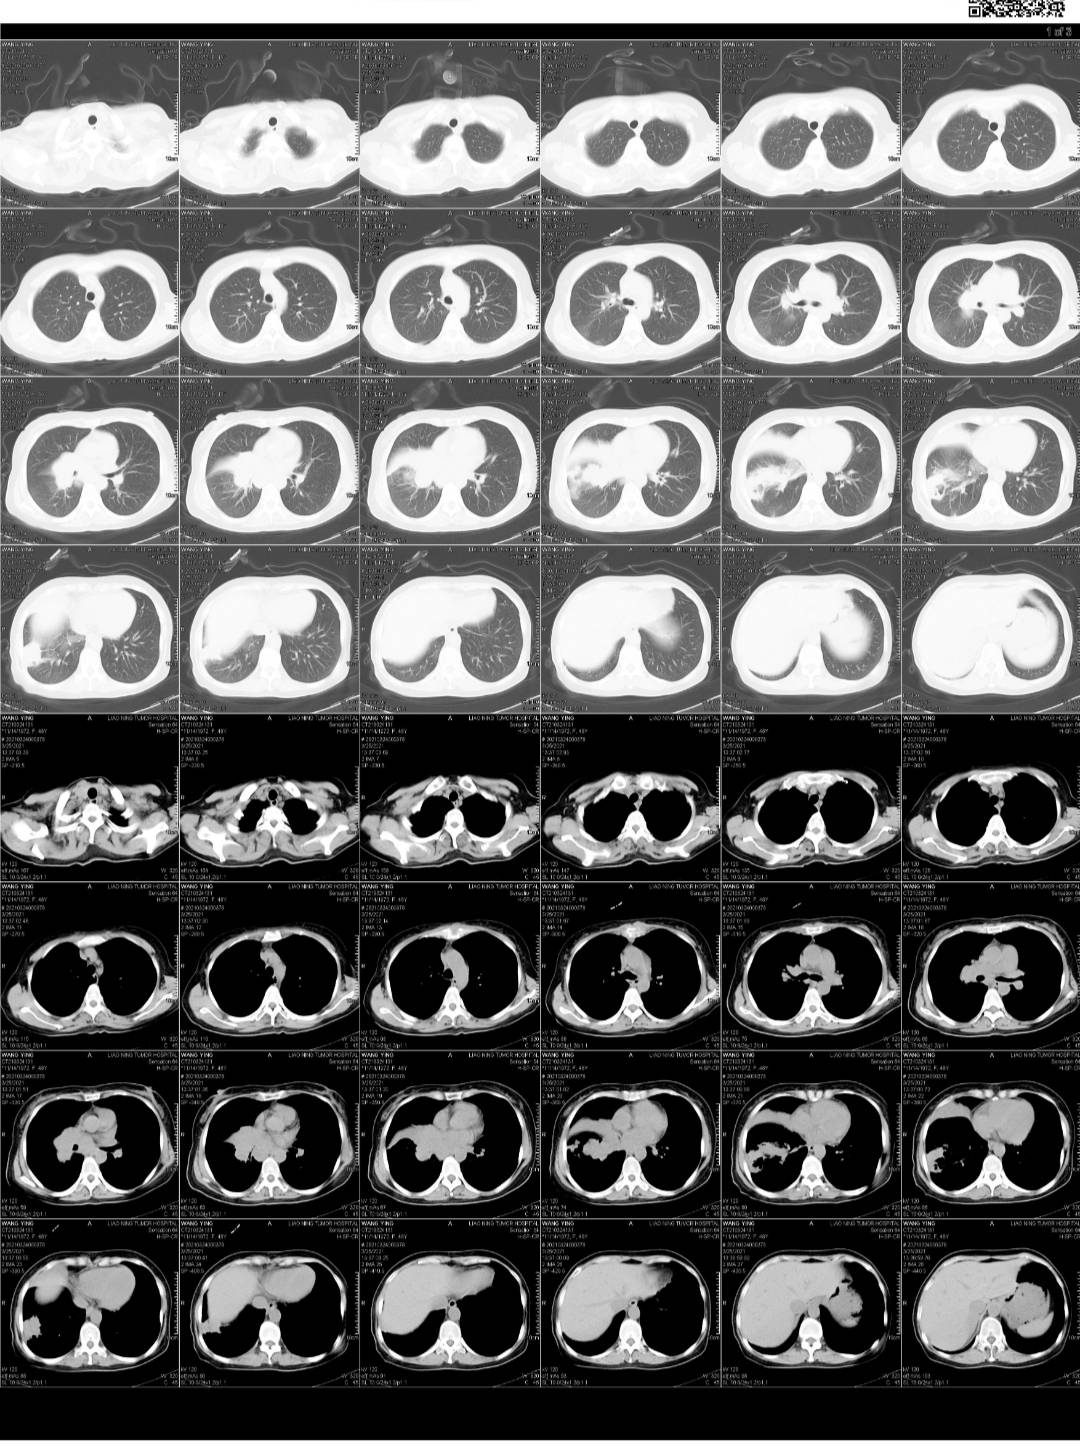

3.24吃一个月凯美纳 复查,打唑来膦酸第二针,当天看到血的结果就觉得不对劲,一些指标还在升高,就跟医生联系,她也觉得不对劲,说等ct再看看。

25号下午做的ct,当天晚上我就在手机上看到了报告,没写大小,感觉不妙,心里非常慌。

今天早上让爸爸取完ct就发给我,真的是没有好转。

下周一穿刺取病理,看看有可能是小细胞吗?